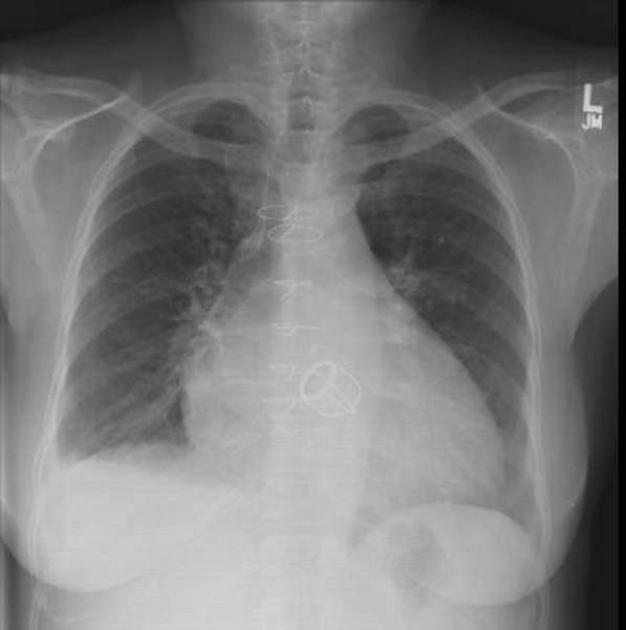

KurdRay

Advanced chest X-ray classification tool that can detect 14 thoracic diseases with AUC of 87%

AI in Radiology

We help reducing errors and misdiagnosis in radiological images with advanced AI models developed locally for your region to have more accurate results